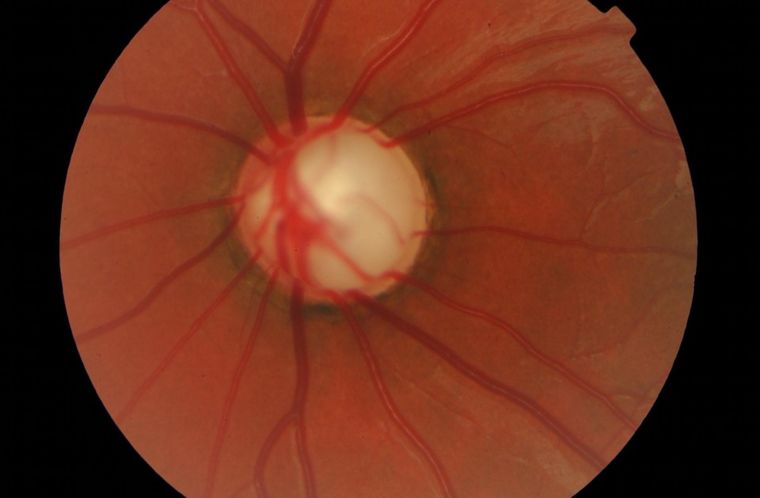

El glaucoma es un grupo de enfermedades en las que se produce un daño progresivo del nervio óptico.

El glaucoma es un grupo de enfermedades en las que se produce un daño progresivo del nervio óptico, que es el encargado de transmitir la información visual al cerebro. Si no se detecta y trata a tiempo, puede provocar la pérdida definitiva de la visión.

Hoy contamos con herramientas que permiten detectar el daño mucho antes de que el paciente perciba cambios en su visión, lo que mejora significativamente las posibilidades de controlar la enfermedad. En este sentido, nuestro centro oftalmológico, cuenta con tecnología de alta complejidad para el diagnóstico y seguimiento del glaucoma, lo que permite evaluar con precisión el estado del nervio óptico y detectar cambios tempranos en la enfermedad.